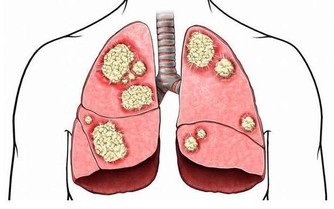

濫用抗生素使越來越多的細菌產生了耐藥,一些原來使用過的很有效的抗生素在對同樣的人及同樣的疾病漸漸失去了效力,使用後感染引起的發熱不退,感染灶也不見縮小或消退。為此,專家們不得不絞盡腦汁,去研究發現對付耐藥菌的新型抗生素。讓人煩惱的是,新抗生素的發現速度遠遠還趕不上細菌產生耐藥的速度,而且耐藥細菌的毒力變得越來越強,越來越難以處置。為了對付細菌的耐藥性,醫生們不得不同時使用多種抗生素,聯合使用對付一個病人正面臨的複雜的感染,當然在殺死有害細菌的同時,一些脆弱的益生菌也會同時被“殺死”,導致機體菌群紊亂,降低機體的抵抗力。